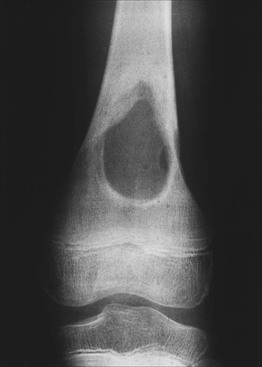

• Localized variant (Fig. 76.2).

Fig. 76.2 Langerhans cell histiocytosis (eosinophilic granuloma of the bone). Radiography of the femur shows a large well-circumscribed osteolytic lesion. Courtesy, Edward McCarthy, MD.

• Often presents as a single, asymptomatic bony lesion (cranium > ribs > vertebrae > pelvis > scapulae > long bones).